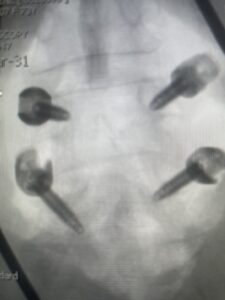

This 73 year-old female had a long history of low back pain and left thigh pain and heaviness of her legs when she ambulated or did activities. She failed all means of conservative treatment including epidurals and PT. On exam she had mild weakness of her left quad but otherwise was intact. Lumbar MRI (Fig 1) revealed significant L4-5 lumbar stenosis and a grade 1-2 spondylolisthesis. Her main pathology was severe, thickened “knobs” of ligamentum forming at the posterior margin of the superior facet processes of L5 and lamina (Fig 2). The patient underwent a decompressive laminectomy of L4 as well as removal of the inferior processes of L5 to widely decompress bilaterally the L4 and L5 nerve roots. Intraoperatively, the descending L5 nerve roots were compressed severely by this severe thickened ligamentum in the subarticular recess. Because of the significant spondylolisthesis we augmented her decompression with fusion. She underwent an L4-5 posterolateral fusion with segmental instrumentation (Fig 3)). Postoperatively she had an uneventful course with relief of her leg pain.

Fig 3: Lateral and AP fluoroscopic images demonstrating placement of pedicle screws for L4-5 fusion for spondylolisthesis.